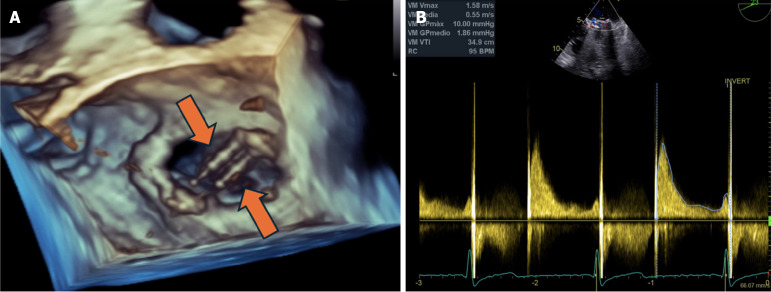

Case summary: We present a case of a 71-year-old female patient with a history of mitral valve replacement and warfarin anti-coagulation therapy. She was admitted to the intensive care unit due to spontaneously reperfused ischemic stroke of probable cardioembolic etiology. A dysfunctional mitral prosthesis was identified due to malfunction of one of the fixed discs. Furthermore, a possible microthrombotic lesion was suspected. Therefore, systemic thrombolysis was performed with subsequent normalization of mitral disc opening and closing.